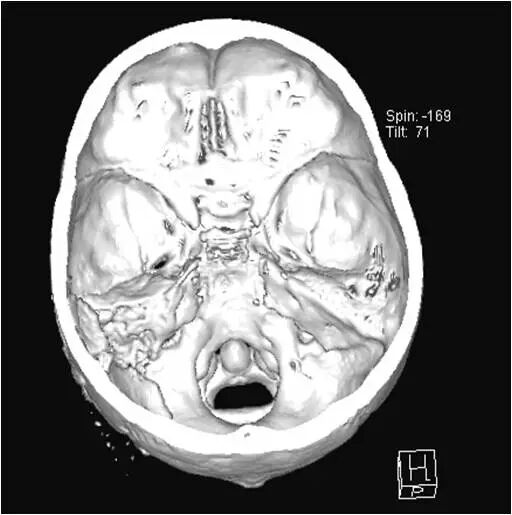

术后颅骨表面重建